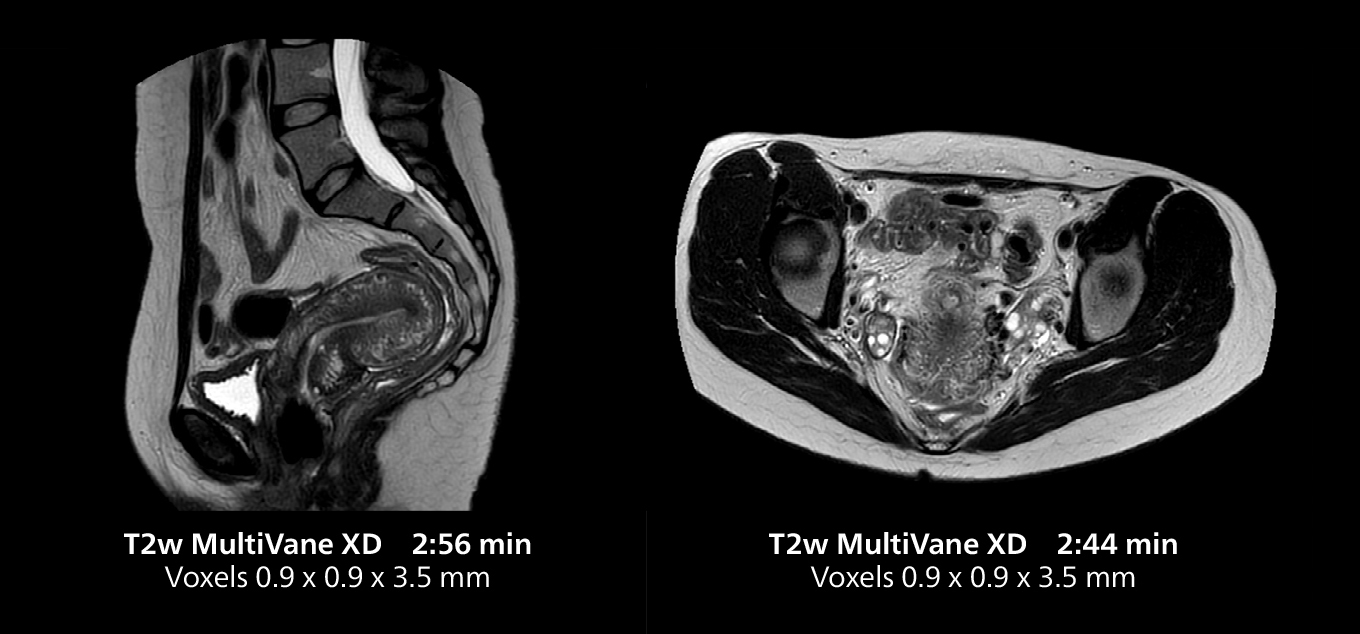

Free-breathing scans provide reproducibility and patient comfort

Dr. Gellée highlights the robust free-breathing scans as “the feature that makes the biggest difference in my daily work. The 3D free breathing sequences are very reproducible, and the axial acquisition is very good. For example, in endometriosis, which is one of my focus areas, it provides high contrast and good resolution so that I can see small details. We also use free breathing for liver and pancreas imaging. In multi-phase liver studies, 4D Free Breathing delivers 3-second temporal resolution, making a dynamic scan with more than one arterial phase possible.”

For elderly patients in particular, free-breathing protocols make exams more comfortable while providing the image quality needed for confident diagnosis. “We have a large elderly population in the city, and because long breath holds are difficult for many older patients, free-breathing is a significant advantage,” Dr. Gellée says. “In cardiac MR for example, with 4D flow and late enhancement, we get excellent diagnostic quality without asking our patients to hold their breath.”

She also uses free breathing with 3D mDIXON to obtain in-phase, water and fat images in a single scan. “It is very reproducible before and after gadolinium, which makes it useful for liver imaging,” she adds.